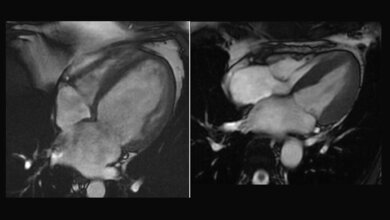

Um die Funktion dieses Gendefekts besser charakterisieren zu können, stellten die Wissenschaftler aus Millionen dieser Herzzellen ein künstliches Herzgewebe her. „Es kontrahiert wie ein richtiges Herz und zieht sich auf elektrische Reize hin zusammen“, sagt Dr. Prondzynski. Ein Zentimeter lang und ein, zwei Millimeter dick war das an HCM erkrankte Laborherz der Forscher, das an Silikonstreifen befestigt in Zellflüssigkeit hing. Um die kranken Herzzellen mit einer gesunden Kontrolle vergleichen zu können, korrigierten die Forscher mithilfe der Genschere (CRISPR/CAS9) die Mutation in den Stammzellen. „So hatten wir gesunde Ausgangszellen, wie von einem gesunden Zwilling“, erklärt Dr. Prondzynski. So entstanden ein krankes und ein gesundes Laborherz für ihre Untersuchungen.

Gefahr für Extraschläge erhöht

Das Ergebnis: Die Kontraktionen der kranken Herzzellen waren stärker und dauerten länger als bei den gesunden. Die elektrische Erregung war deutlich in die Länge gezogen. Als zugrunde liegenden Mechanismus vermuten die Wissenschaftler, dass der winzig kleine neu erkannte Gendefekt bewirkt, dass das für die Zellstruktur verantwortliche Protein fehlerhaft ist und seine Funktion nicht richtig ausüben kann. Das hat dann wiederum zur Folge, dass vermehrt Kalziumionen in die Herzzellen einströmen und die elektrische Erregungsleitung und Kontraktionszeit verlängern. Damit erhöht sich die Gefahr für Extraschläge. „Dies könnte ein Grund für Herzrhythmusstörungen bei HCM-Betroffenen sein“, so Dr. Lemoine.